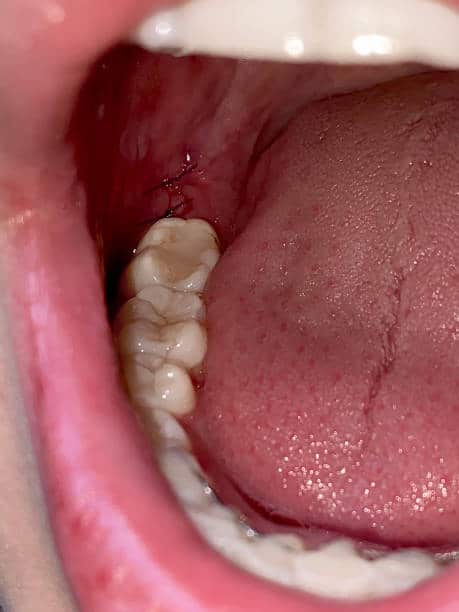

The Wisdom Tooth Removal Procedure

- Initial Consultation : The process begins with a thorough consultation, digital X-rays, and a detailed discussion of your treatment plan.

- Preparation : Local anesthesia or sedation is used to ensure a comfortable, pain-free experience.

- Extraction : The tooth is gently removed, sometimes through a small gum incision. Stitches may be placed if needed.

- Aftercare : You’ll receive clear instructions to manage pain, reduce swelling, and maintain oral hygiene for smooth healing.